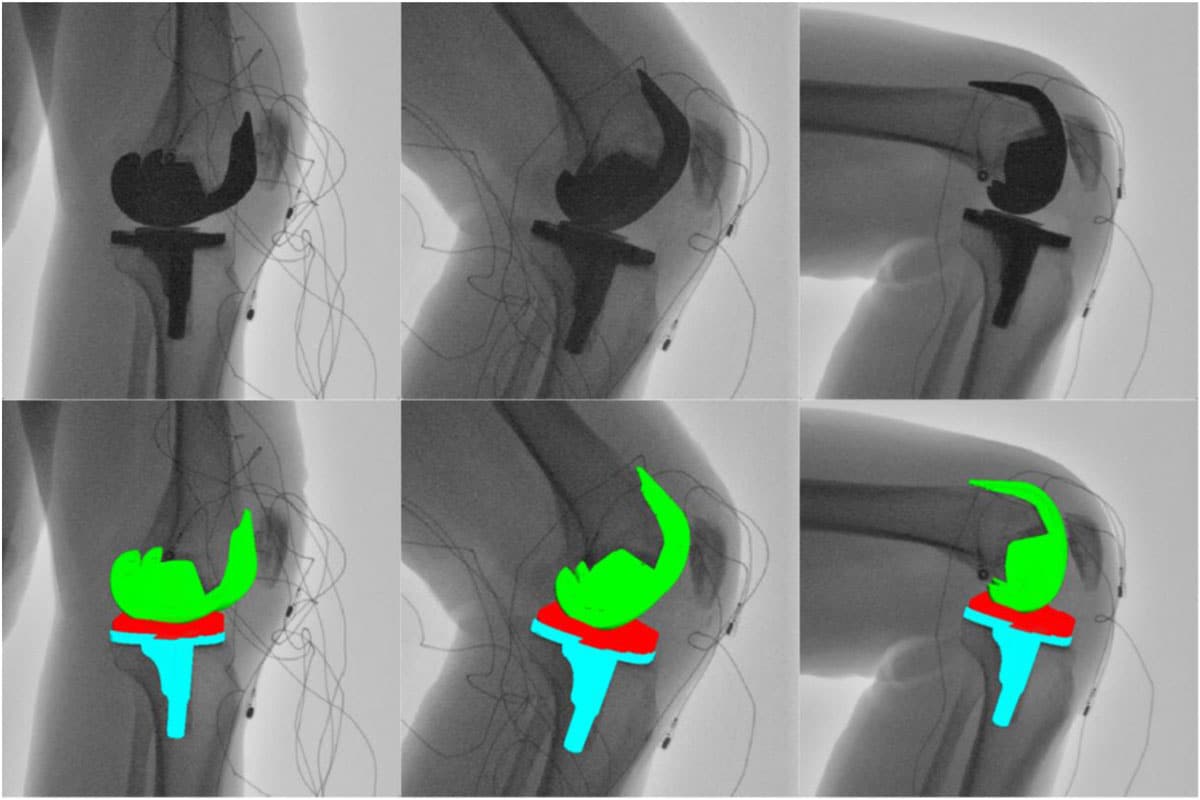

Anteriorly Stabilized Total Knee Arthroplasty

Total Knee Arthroplasty (TKA) involves the replacement of damaged bone and cartilage within the knee joint to alleviate joint pain and restore overall function to the patient. Unfortunately, to properly expose the joint during surgery and to create space in the knee for the components themselves, surgeons must resect key stabilizing soft tissues within the joint, notably the anterior cruciate ligament (ACL) and the posterior cruciate ligament (PCL). With these stabilizing structures removed, the implanted knee is subject to instability and paradoxical sliding.

The University of Tennessee’s Center for Musculoskeletal Research is working with industry-leading orthopaedic companies to design mechanical constraints to replace the functionality of these key ligaments. Notably, a novel TKA design, the “Bi-Cruciate Stabilized” TKA, incorporates a unique cam-and-post mechanism that strives to replicate the constraints that the ACL and PCL provide. The effectiveness of these design features is still under investigation, but early in vivo fluoroscopic studies demonstrate stable overall kinematics during both flexion and extension-based activities, indicating a promising future for stable TKA.